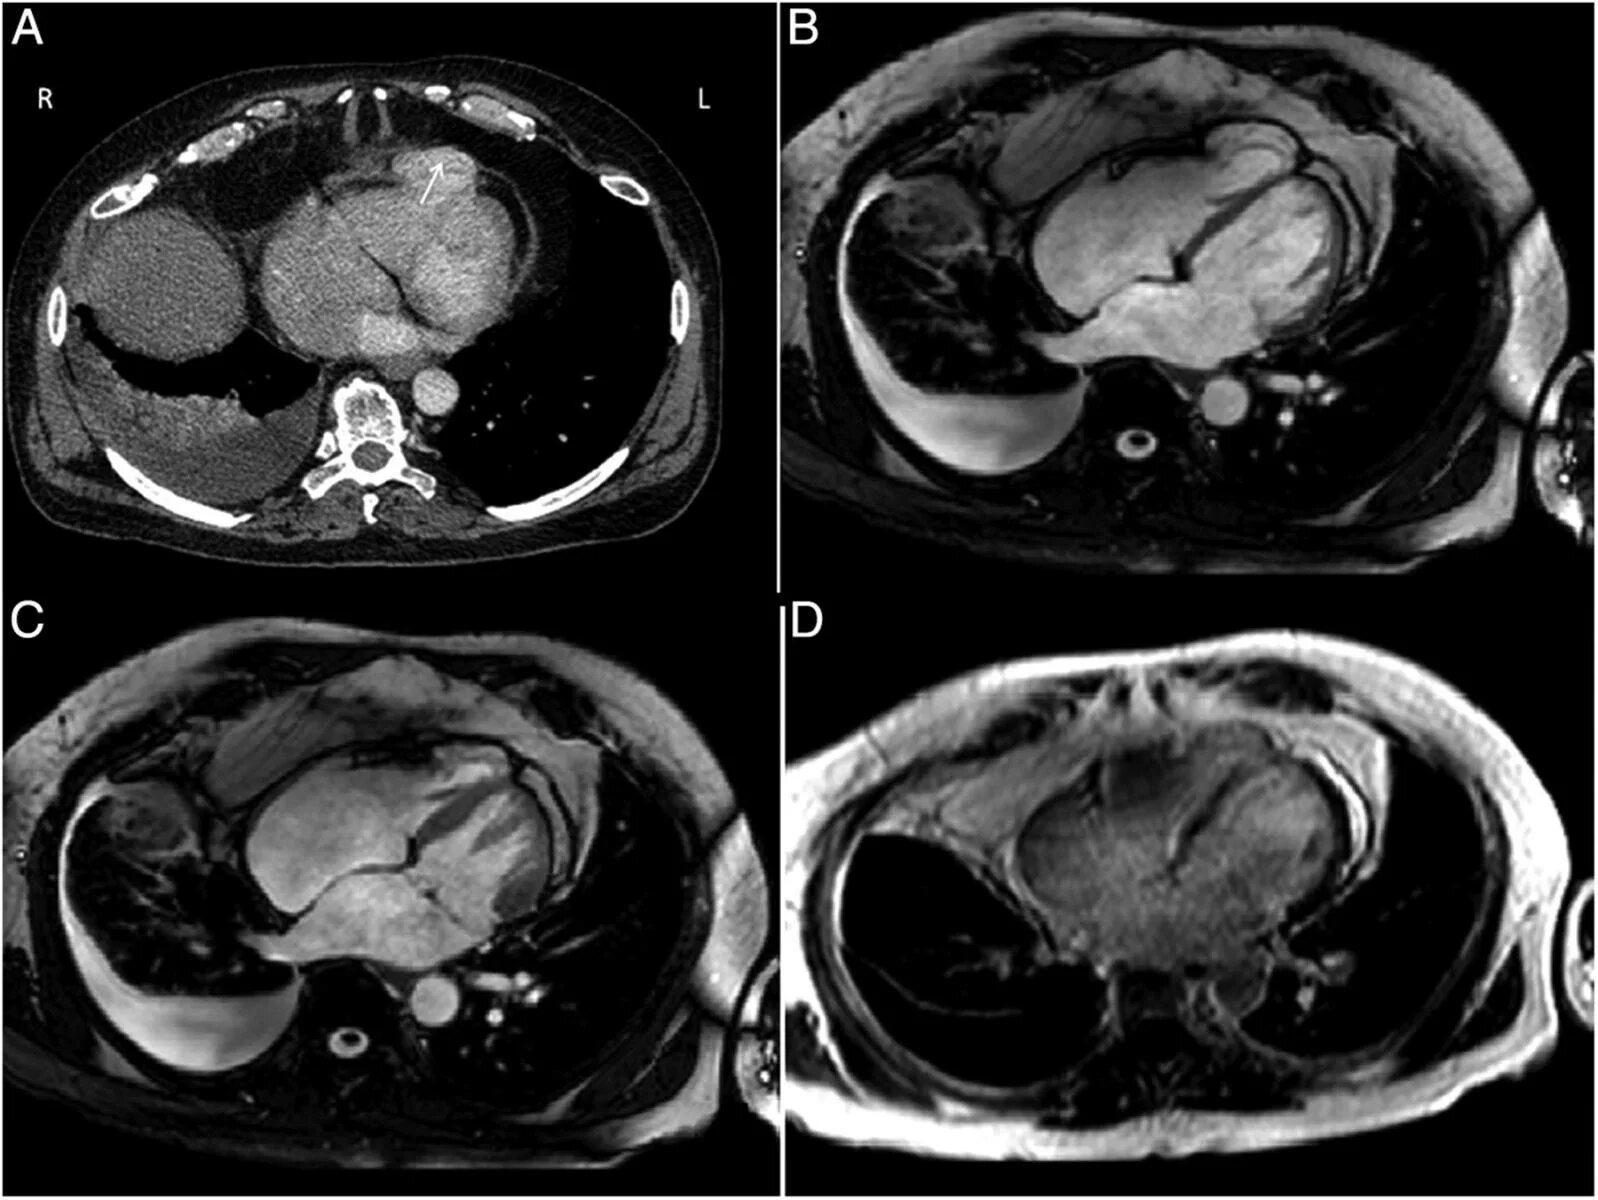

Как делают кт сердца